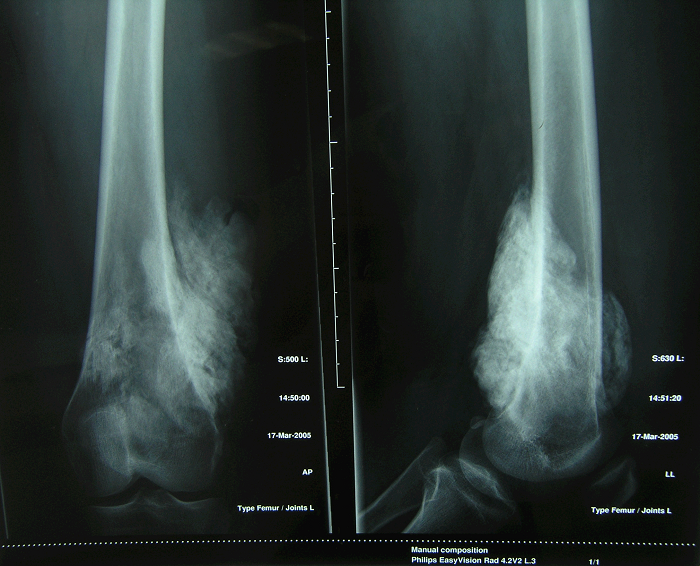

2、病例2:女 10岁 左股骨下端普通型骨肉瘤并病理性骨折,大剂量化疗后行肿瘤边缘切除定制型假体置换术,术后局部复发截肢,2年后肺转移死亡。

图 7术前X线片

a:正位 b:侧位